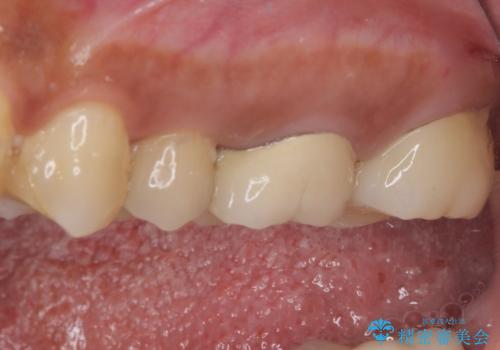

後日状態を確認したところ、残された神経に異常がなかったため、セラミッククラウンにて補綴治療を行いました。